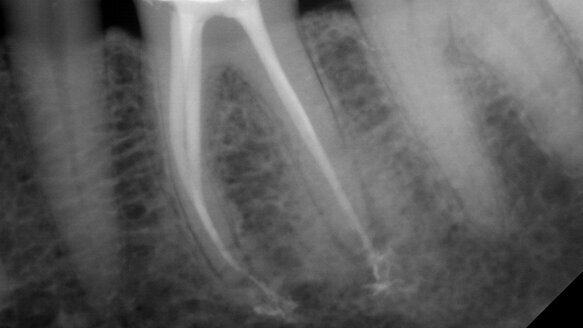

Hand files allow the clinician to manually “feel” the unseen dimension in canal anatomy beyond what radiographs alone can illustrate. Specifically, by virtue of hand-file resistance to apical advancement, the clinician can, by tactile feel, determine the curvature, calcification, length, the anatomy of the MC, and if iatrogenic events may have occurred. Only cone-beam technology comes close to providing the tactile information provided by hand files (Planmeca).

Such tactile information helps determine treatment strategies prior to shaping. Astute RNT use has, as its foundation, intimate canal knowledge first by hand files. Forcing RNT files to length without adequate hand-file negotiation and a glide path is the harbinger of file fracture, canal transportation and inadequate cleaning and shaping.